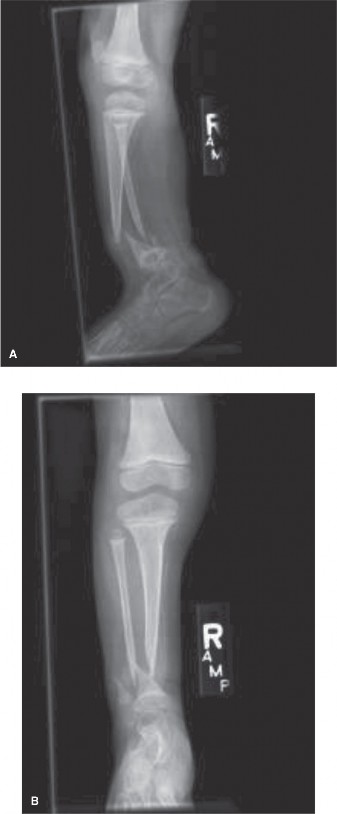

Initial anteroposterior and lateral radiographs of the right tibia and fibula were obtained. These revealed significant anterolateral bowing of the right tibia and fibula, centered at the junction of the middle and distal thirds.

The radiographic analysis demonstrated profound diaphyseal narrowing at the apex of the deformity. The medullary canal was completely obliterated by dense sclerotic bone at the apex of the bow, a classic radiographic hallmark of impending congenital pseudarthrosis of the tibia. According to the Crawford Classification system, this presentation aligns with a Type II deformity, characterized by anterolateral bowing with medullary sclerosis, though early cystic changes were visible on the lateral projection, suggesting a transition toward a Type III lesion.

The fibula also demonstrated concomitant anterolateral bowing, which is a critical prognostic factor. Fibular involvement dictates the necessity of addressing both bones during surgical reconstruction to prevent recurrent deformity and ensure adequate stabilization of the ankle mortise. The mechanical axis of the lower extremity was significantly deviated laterally and anteriorly, resulting in a severe malalignment that exponentially increases the bending moments across the dysplastic tibial diaphysis during the stance phase of gait.